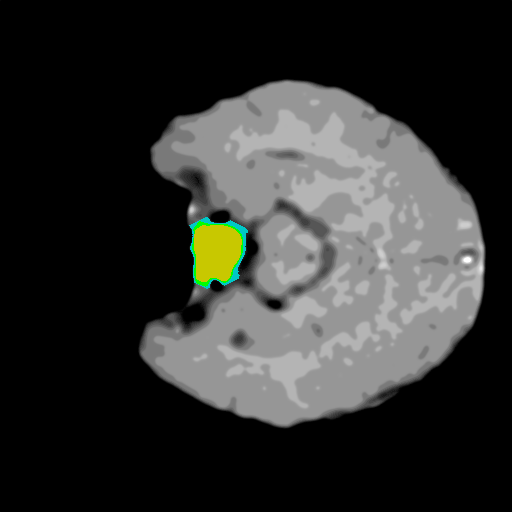

Extensive experiments have been performed in the current setup, and experimental outcomes are reported with the demonstration of numerical and statistical analyses using the proposed QFS-Net, QIS-Net [39], convolutional U-Net [18] and Residual U-Net (URes-Net) architectures [20]. The human expert segmented skull-tripped contrast enhanced DSC brain MR input image slices of size and ROIs are provided in Figure 5 as samples. The demonstration of QFS-Net segmented images followed by the essential post-processed outcome on the slice no. for class level with four distinct activation schemes () are shown in Figure 6. It is evident from the experimental data provided in Table LABEL:tab1 that the proposed QFS-Net performs optimally for the -connected quantum fuzzy pixel information heterogeneity assisted activation () with and gray scale set in comparison with other thresholding schemes and gray scale sets under the four evaluation parameters () [44]. The segmented tumors obtained using the proposed self-supervised procedure under class transition levels with four different thresholding schemes , , and are demonstrated in Figures 7- 8 for the class boundary sets and [39], respectively. The segmented images using the remaining two class boundary sets ( and ) [39] are provided in the supplementary materials section. The segmented ROIs describing the whole tumor region after the masking procedure using QIS-Net, U-Net and URes-Net are also reported in Figure 9.